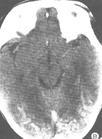

急性硬腦膜下血腫2.頭部CT應作為首選檢查專案,具有簡便、安全、可在短時間內顯示血腫的位置、大小和數目等優點,對於額葉底、顳葉底和兩側性血腫的診斷往往較腦血管造影更具有優越性,可以減少血腫的漏診。

CT掃描內板下透鏡狀高密度影硬腦膜下及腦內不規則高密度影病變區呈低密度影。